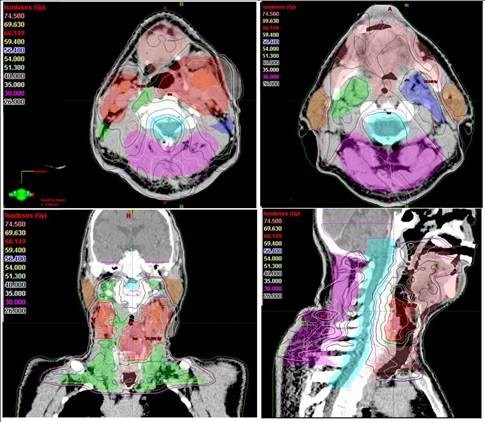

Son yıllarda yapay zeka uygulamalarının kanser alanında kullanılmasına yönelik araştırmalarda artış olduğunu ifade eden Prof. Dr. Yavuz, “Tümör ve çevredeki normal dokuların üç boyutlu olarak sınırlarının çizildiği bu süreç, bir hastanın tümör bölgesine ne kadar radyasyon alacağını ve ışının en uygun nasıl odaklanacağını belirler. Özellikle ABD’nin Ulusal Sağlık Enstitüsünce desteklenen önemli bir araştırma projesinde "Yapay Zeka’ kullanarak yüksek riskli tümör hedef hacimlerinin sınırlarının 3 boyutlu olarak belirlenmesi için her bir görüntüleme film kesitinde tümör ve normal doku sınırlarının tek tek çizilmesi (konturlama) işlemlerini otomatikleştirmek için yeni bir yöntem geliştirildi” dedi.

Bu çalışmanın sadece yüksek riskli tümör hacimlerinin ’Yapay Zeka’ ile otomatik bir şekilde ve çok yüksek doğrulukta belirlenmesine yönelik olduğunu dile getiren Prof. Dr. Yavuz, "Bir sonraki aşamada, eldeki tüm veriler birleştirilerek, orta ve düşük riskli tümör bölgelerinin de otomatik ve en doğru bir şekilde belirlenmesi mümkün olabileceği gibi, hastaya özgü en uygun radyoterapi veya kemoterapiyi de ayarlamak adına çeşitli genetik mutasyonlara ait bilgiler de bu yapay zeka uygulamasına entegre edilebilecektir. Bu şekilde, kanser tedavisi sonuçlarında başarı oranlarının artması da kaçınılmazdır. Yöntemin çok önemli bir avantajı da bizlere sunduğu yüksek hız ve verimliliktir. Normalde, örneğin bir baş boyun kanserinde, hedeflenen hacimleri belirlemek bir hekimin 1-4 saatini alır. Yapay Zeka kullanan özel bilgisayar sistemi ile hem bir dakikadan kısa bir sürede hedef hacimler belirlenebiliyor, hem de hekimden hekime değişebilen hata payları ihtimali tümüyle ortadan kalkıyor. Bu yöntem, özellikle, hedef hacim belirleme alanında tecrübeli uzman sayısının daha az olduğu düşük ve orta gelir düzeyindeki ülkelerde çok büyük bir kolaylık sağlayacaktır, ancak bu yöntemin ABD gibi gelişmiş ülkelerde de kanser tedavilerindeki yararlılık ve verimliliği çok artıracağı açıktır" şeklinde konuştu.